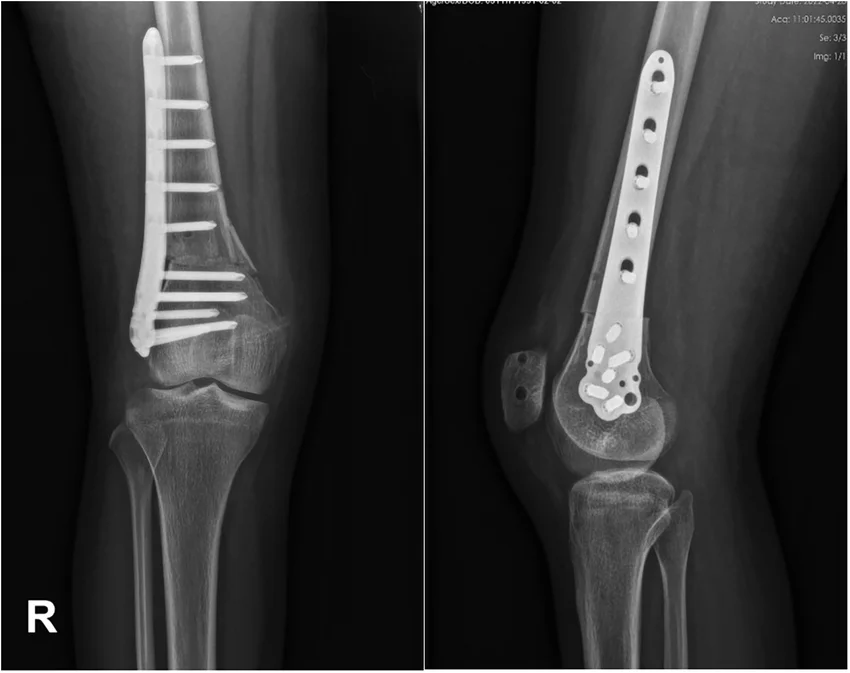

In some cases, MPFL reconstruction may be combined with other procedures, such as a tibial tubercle osteotomy (TTO), to better correct the alignment of the kneecap and reduce the risk of future dislocations.

Concurrent procedures

If there are other contributing anatomical abnormalities, such as patella alta or lateral maltracking, Dr Awwad may also consider combining MPFL reconstruction with procedures such as:

Fixation

The graft is typically fixed to the patella using small anchors or tunnels, and to the femur using an interference screw or other fixation device. The goal is a strong, stable reconstruction that mimics the native ligament’s function while preserving the patient’s natural anatomy as much as possible.